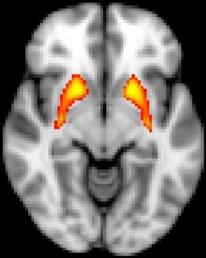

In research conducted at the Mizzou Brain Imaging Center and using a feedback-based learning task, Kerns and his team found that people at risk for psychosis are impaired when they need to rely on feedback to learn. Using fMRI brain scans, the team found that people at risk for psychosis failed to activate the striatum when they received feedback.

"Current research suggests that people like John Nash develop delusions in part because they have problems learning from feedback, like a car driving without a brake," Kerns said. "Our research is also consistent with other research that people with psychosis have an increased level of dopamine in the striatum. However, for the first time we have linked psychosis risk to both a behavioral impairment, poor feedback learning, as well as striatum dysfunction."